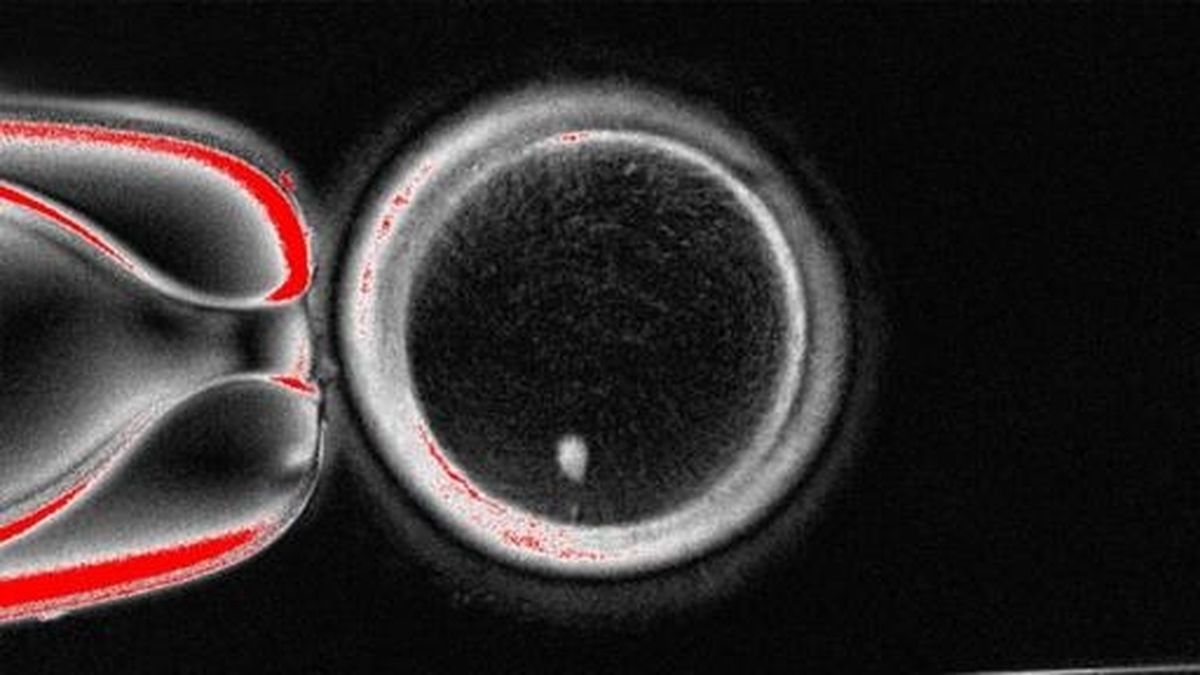

The researchers produced 82 functional human oocytes, or immature egg cells. Next, these lab-generated eggs were fertilized with donated sperm in petri dishes. The results were cautiously promising: about 9% of the fertilized eggs survived for five to six days, developing to the blastocyst stage—the point at which embryos are typically transferred to the uterus during in vitro fertilization (IVF). As Dr. Mitalipov explained to NPR, “It’s a significant step forward.”

Yet, the breakthrough comes with a critical caveat. All embryos created in the study were chromosomally abnormal. According to Dr. Paula Amato, coauthor and professor of obstetrics and gynecology at OHSU, “All the resulting embryos were chromosomally abnormal, either because they had the wrong total number of chromosomes or not one from each pair.” These abnormalities, which stem from the challenges of correctly reducing chromosome numbers in the reconstituted eggs, mean that none of the embryos would be suitable for implantation or could result in healthy babies.